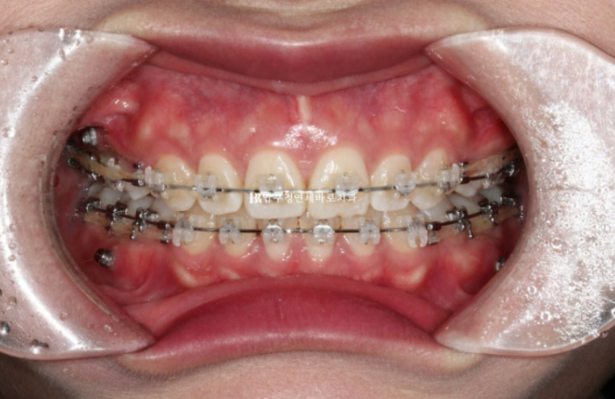

23.09

치료시작 7개월째 모습입니다.

이제 막 발치공간이 없어지면서 앞니가 뒤로 들어가기 시작하는 단계입니다.